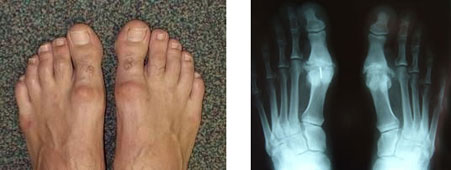

Nódulo duro formando um aspecto de “calo” na superfície dos pés.

Nos raios-x, observamos a articulação “deformada”, “inchada”, e sem espaço entre os ossos da articulação metatarsofalangiana.

Novamente, observamos a articulação “deformada”, “inchada”, e sem espaço entre os ossos da articulação metatarsofalangiana, além de osteófitos laterais.